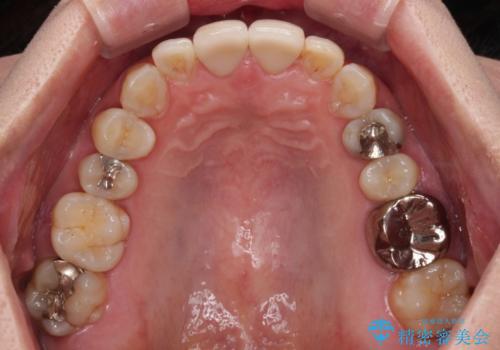

- つぎはぎのある前歯のセラミックの色合いが気になるとのことで来院された患者様です。

グレーの色が透けて見える気がする点が気になっていらっしゃり、やや黄色みのある色を希望されていました。

仮歯に置き換えた後にオールセラミッククラウンにて補綴治療を行うこととしました。